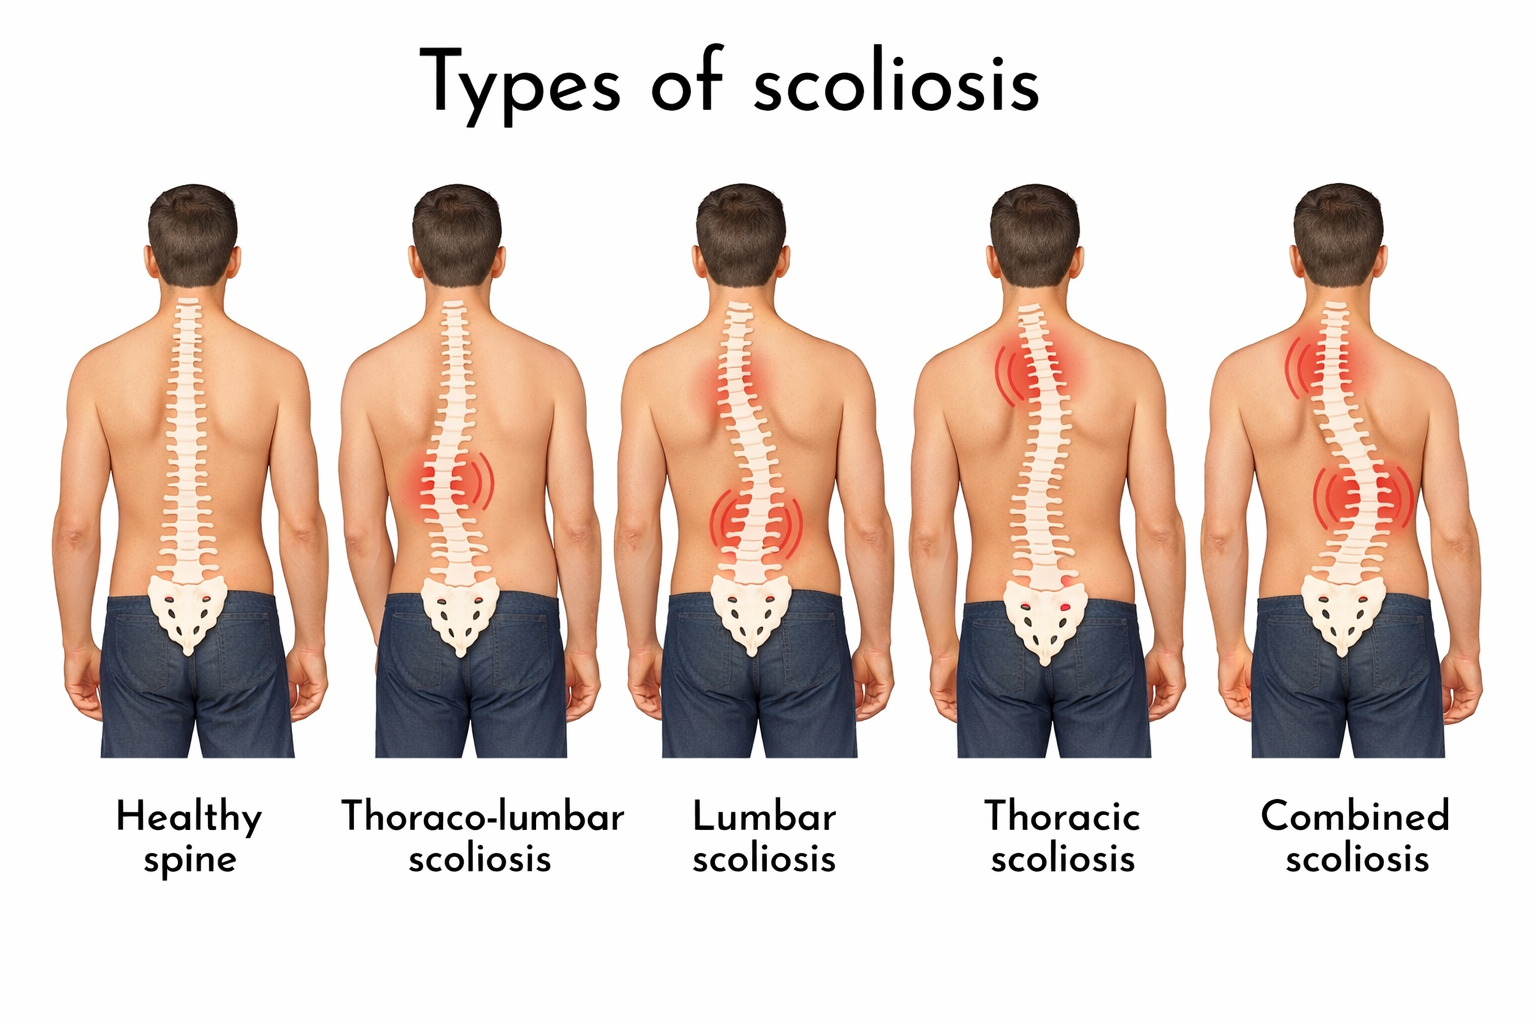

Scoliosis &

Spinal Deformity

Curvature · Alignment

- Complex: scoliosis and adult spinal deformity, spinal tumors, spinal trauma, failed back surgery syndrome.